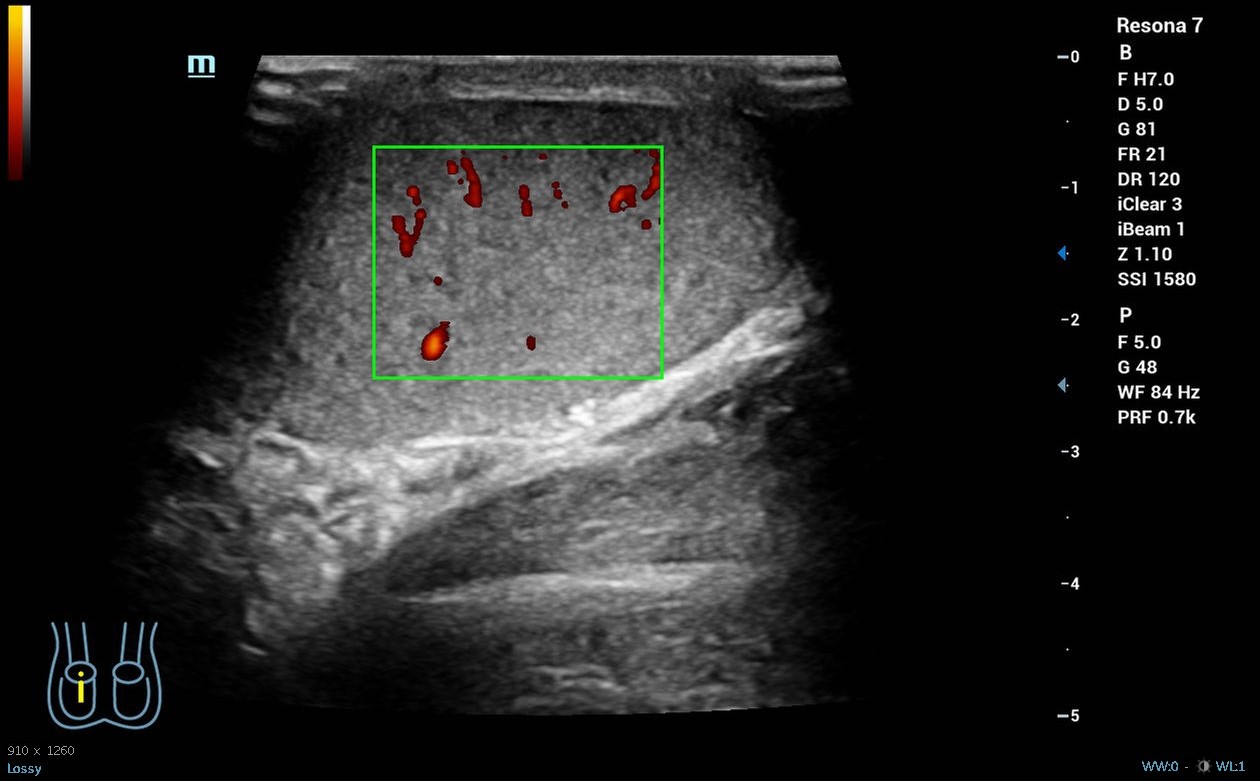

Hombre de 19 años sin antecedentes de interés que acude a la guardia del centro de salud por dolor súbito en el testículo derecho desde las 04.00 h que le ha despertado, asociado a náuseas y vómitos, sin otra clínica infecciosa o traumática acompañante. A la exploración física presenta abdomen normal, pero teste izquierdo ascendido y horizontalizado, doloroso a la palpación, con discreto aumento de tamaño o cambios en temperatura, con signo de Prehn negativo y reflejo cremastérico ausente en lado izquierdo. Se realiza ecografía clínica, donde se objetiva testículo izquierdo aumentado de tamaño con morfología y ecoestructura normal, pero con ausencia de flujo power-Doppler en su interior, ligero hidrocele y aparente giro del cordón espermático en su porción distal.

Derivación hospitalaria urgente, donde se corroboran los hallazgos de la ecografía clínica y se realiza detorsión quirúrgica.